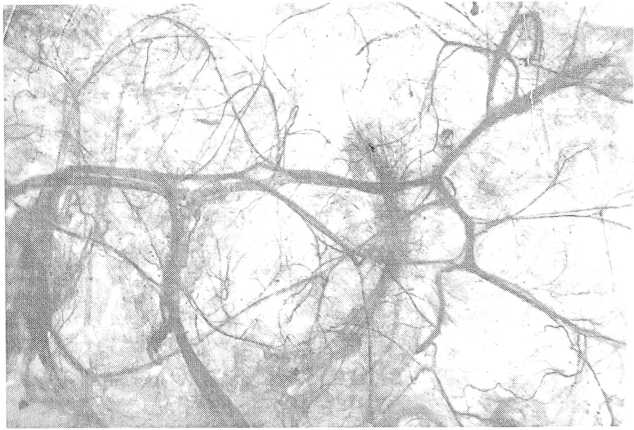

Богатейшие по численности вены, в которых была обнаружена красящая масса, определялись в забрюшинной клетчатке (рис. 5). В ней, наряду с крупными венозными сосудами, относящимися к системе нижней полой вены, определялись сети мельчайших вен, ориентированных в различных направлениях.

Рис. 5. Вены забрюшинной клетчатки